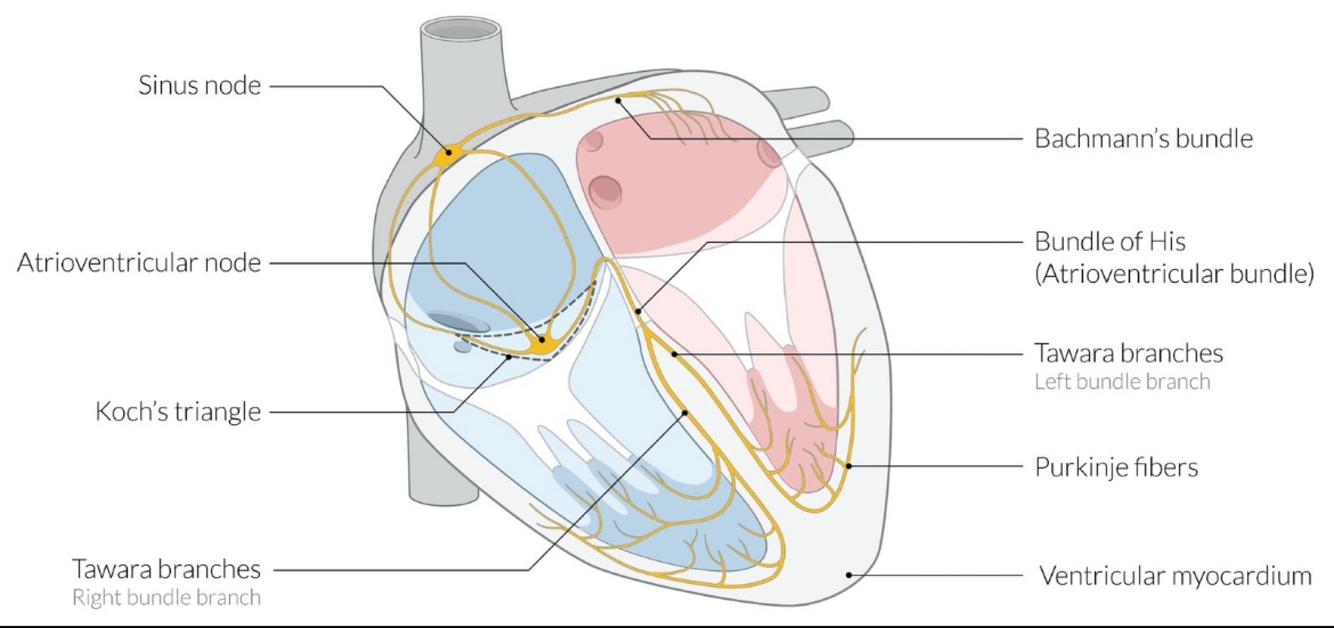

La disnea de este paciente, los mareos, los episodios sincópicos (ataques de Stokes-Adams), la bradicardia, el infarto de miocardio inferior (IM) reciente y los hallazgos del ECG son consistentes con un bloqueo auriculoventricular de tercer grado (es decir, bloqueo AV completo). Esta condición se caracteriza por la disociación AV, en la que las aurículas (ondas P) y los ventrículos (complemples QRS) laten independientemente entre sí. Los bloqueos AV de tercer grado ocurren debido a la conducción deteriorada a nivel del nodo AV (~ 20%), haz de His, o por debajo del haz His (más común; ~ 60%). Un bloque por encima del haz His está asociado con complejos QRS estrechos (< 120 ms), mientras que un bloque debajo del haz His se caracteriza por complejos QRS anchos. Además, la frecuencia auricular es mayor que la frecuencia ventricular (es decir, más ondas P que complejos QRS) y tanto las frecuencias auricular como ventricular son constantes.

El bloqueo AV de tercer grado puede complicar un IM inferior (porque el nodo AV y su haz son suministrados principalmente por la arteria coronaria derecha) o un IM anterior (porque el haz His puede recibir sangre de las ramas septales de la arteria coronaria izquierda). Otras causas del bloqueo AV de tercer grado incluyen infecciones (por ejemplo, enfermedad de Lyme, endocarditis bacteriana), miocardiopatía, hiperpotasemia y efectos iatrogénicos (por ejemplo, intervenciones cardíacas, medicamentos como betabloqueantes).

En el bloqueo cardíaco completo, los impulsos eléctricos del nodo SA no se conducen a los ventrículos. Los miocitos de la vía de conducción cardíaca tienen el potencial de despolarizar espontáneamente y comportarse como marcapasos cuando no reciben señales del nodo SA, lo que resulta en ritmos de escape. Dependiendo de la forma de los complejos QRS de los ritmos de escape, se puede determinar el sitio de estos marcapasos ectópicos. Los complejos QRS normales y estrechos como se ve en este ECG son desencadenados por impulsos en cualquier lugar desde el nodo SA hasta el haz de His (es decir, el bloque está en o proximal al haz de His).